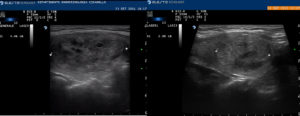

Immagini ecografiche pre trattamento e a due anni di follow-up in cui si evidenzia la riduzione del nodulo

Immagini per gentile concessione del Dott.ssa Rago (Ospedale Cisanello, Pisa)